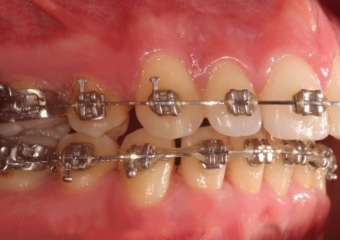

Mordida após a cirurgia